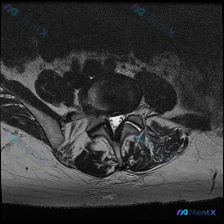

腰椎MRI轴位读片:这个典型多因素椎管狭窄你能看出来吗?

今天拿到这个腰椎轴位T2加权MRI,正好整理一下读片和分析思路,分享给大家。

提供的是腰椎MRI T2加权轴位影像,没有侧位定位像和矢状位序列,我们先基于现有信息分析:

- 定位:从椎体形态、关节突位置、硬膜囊结构来看,这个层面大概是L4/L5或者L5/S1椎间盘水平,具体节段需要后续结合矢状位确认

- 影像遵循医学成像标准方位:图像右侧对应患者左侧,左侧对应患者右侧

椎间盘相关

- 髓核信号明显降低,呈现典型的「黑盘征」,这是椎间盘脱水退变的特征性表现

- 椎间盘向后方弥漫性隆起,边缘已经超出了椎体后缘连线,整体形态不对称

椎管和神经结构

- 中央椎管明显狭窄,硬膜囊受压变形,正常的椭圆形/圆形被压成了类似「三叶草」的形态;硬膜囊周围的脑脊液高信号空间几乎消失,有效椎管容积明显受限

- 双侧侧隐窝都有显著狭窄

- 双侧神经根周围的脂肪间隙已经受压消失,显示不清,提示神经根已经受到挤压

骨性结构和软组织

- 椎体后缘可以看到骨赘形成(骨质增生),是加重狭窄的结构性因素

- 双侧关节突关节肥大增生,关节间隙模糊,符合退行性关节炎改变

- 黄韧带存在增厚,这是导致椎管后方狭窄的主要软组织原因

第一印象初步判断

看到椎间盘信号降低+弥漫后膨+多结构增生,首先考虑退行性脊柱病变,接下来我们一步步收敛排查。

关键线索拆解

这个病例的关键点在于:不止椎间盘有问题,骨、关节、韧带都有异常,是多结构共同导致的狭窄,不能只盯着椎间盘看。

退行性椎间盘病变伴腰椎管狭窄

- 支持点:黑盘征(椎间盘脱水)、椎间盘弥漫膨隆、椎体骨赘、关节突增生、黄韧带肥厚,所有征象都符合慢性退行性改变,多因素共同导致中央管+侧隐窝狭窄,彼此相互印证,逻辑自洽

推理收敛

所有的异常表现都可以用「退行性腰椎疾病」这一个病理过程解释,符合一元论诊断原则,其他病变没有足够的支持证据,因此可以把方向收束到退行性病变上来。

整体结论

结合现有影像信息,最符合的诊断是退行性腰椎管狭窄症,是由多因素共同导致的狭窄:

- 软性致压因素:椎间盘膨隆/突出

- 硬性致压因素:椎体后缘骨赘、关节突关节增生、黄韧带肥厚

- 狭窄范围:同时累及中央椎管和双侧侧隐窝,狭窄程度明显